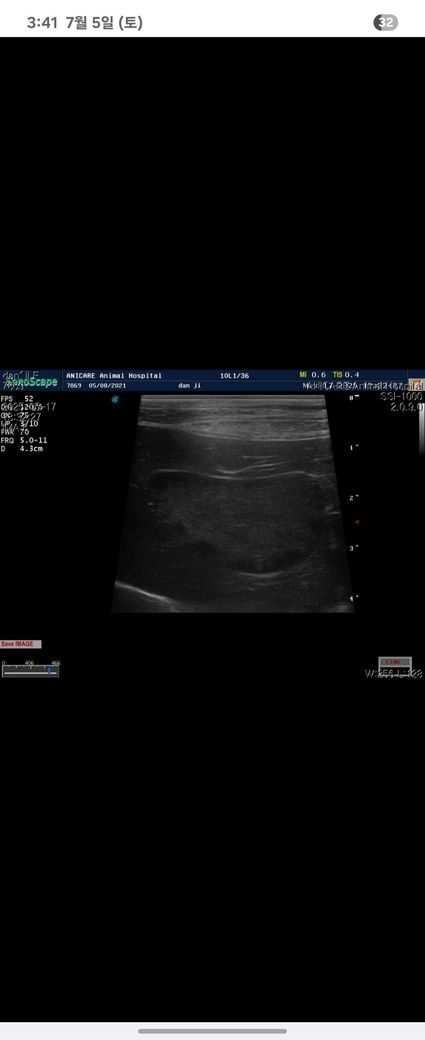

4살 강아지

건강검진에서 담낭슬러지를 발견했어요

어린데 담낭슬러지가 심하다고